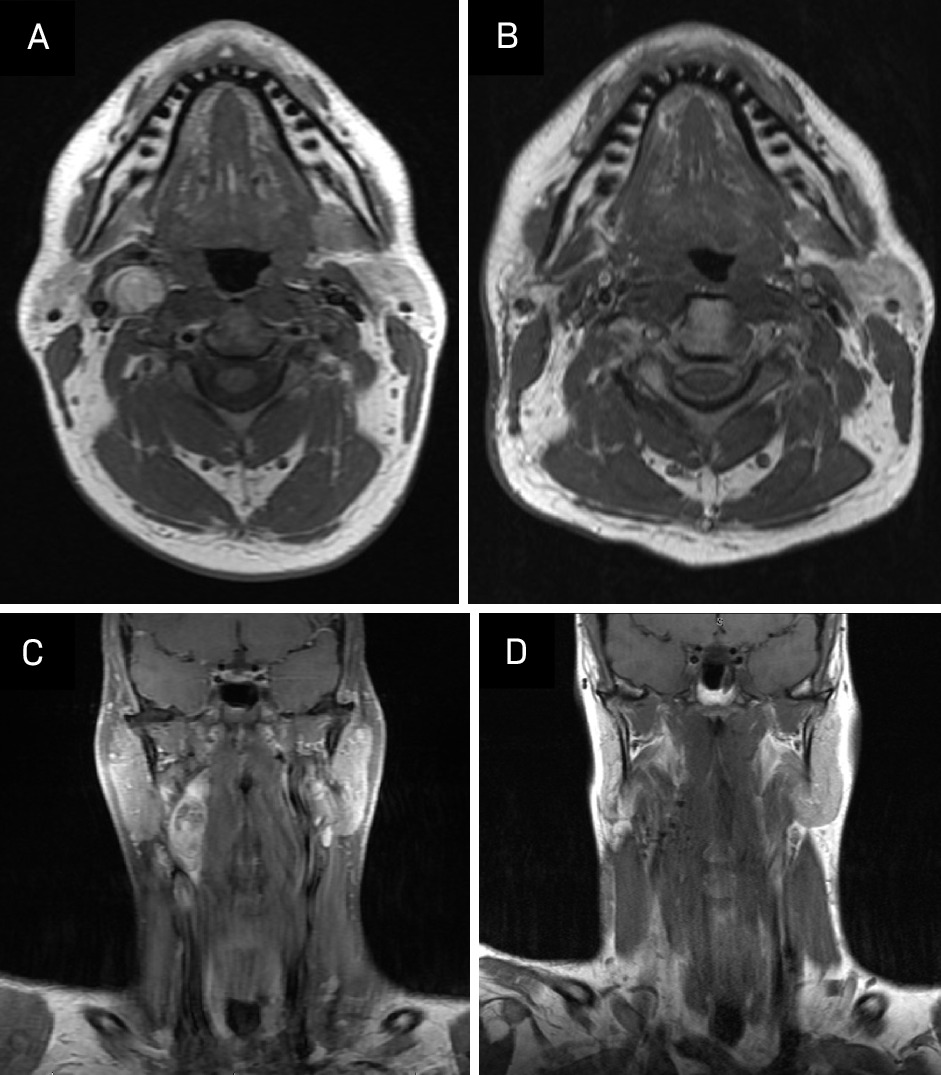

MRI 3 months post-treatment demonstrated no evidence of local or regional recurrence. Imaging showed increased signal on STIR and some enhancement in the right aspect of the neck, including the right aspect of the oropharynx and supraglottic larynx, presumably postradiation effects. There was also increased T2 signal and enhancement in the right submandibular gland, which was also compatible with postradiation effects (Figure 6). We plan to repeat MRI every 6 months for 2 years and then yearly for 5 years. Routine clinical follow-up will be scheduled after every imaging study.